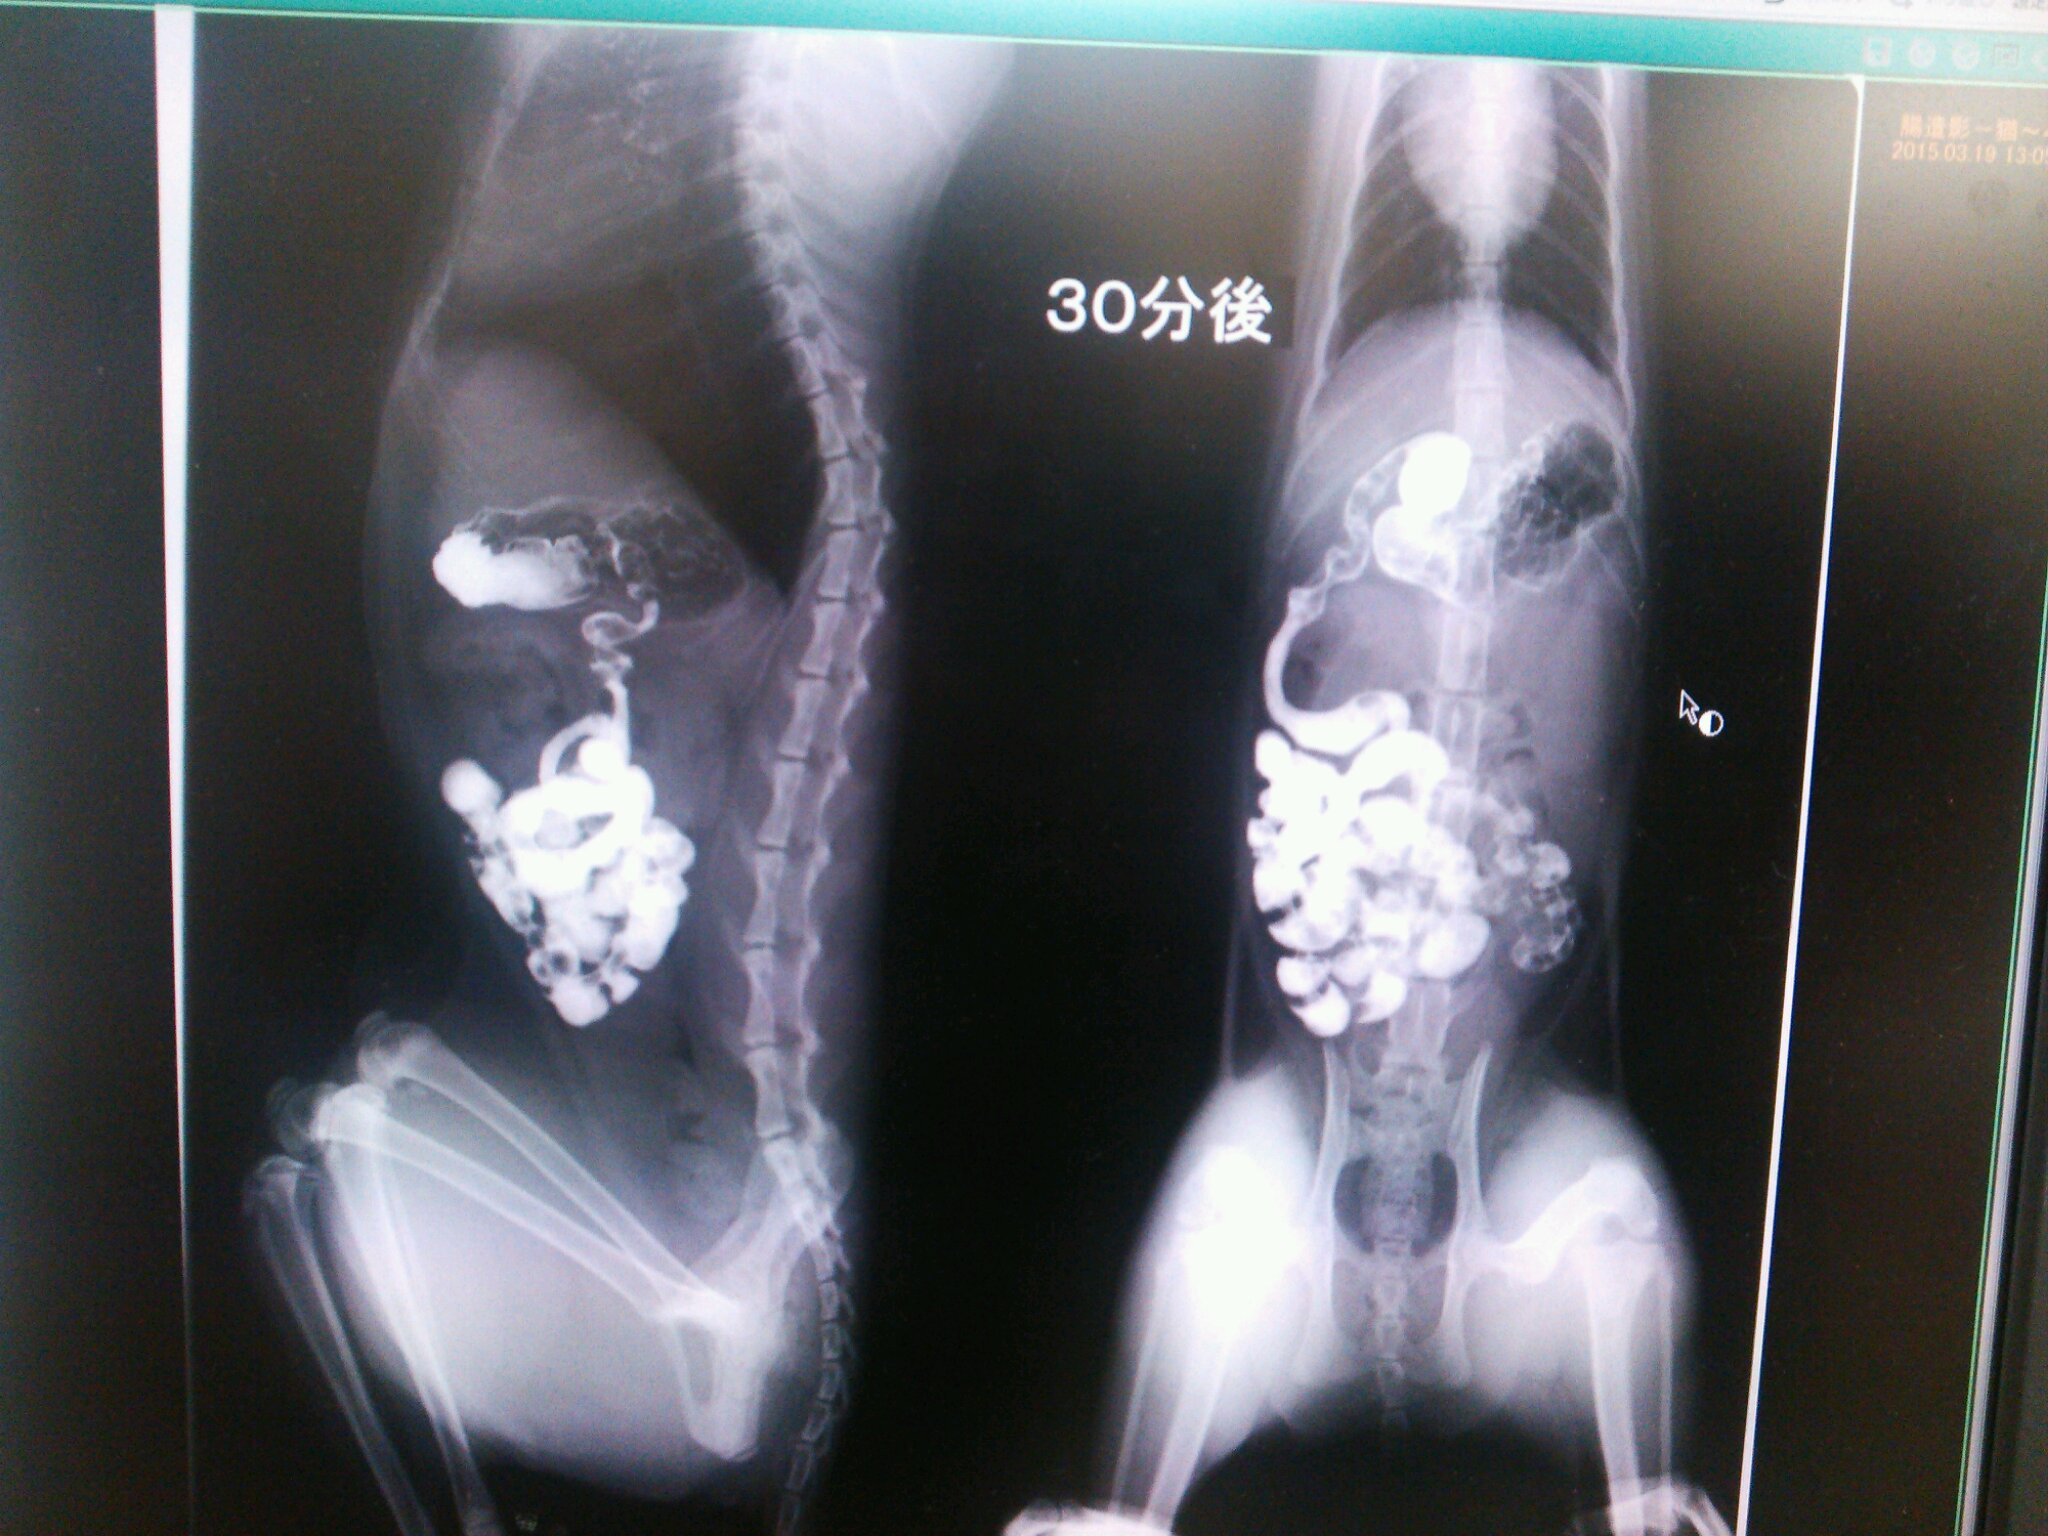

こんなカンジでバリウムが流れていって

どっかで止まれば、そこが腸閉塞っつー話でやんすた。

こんなことを5時間以上続けたらしい。